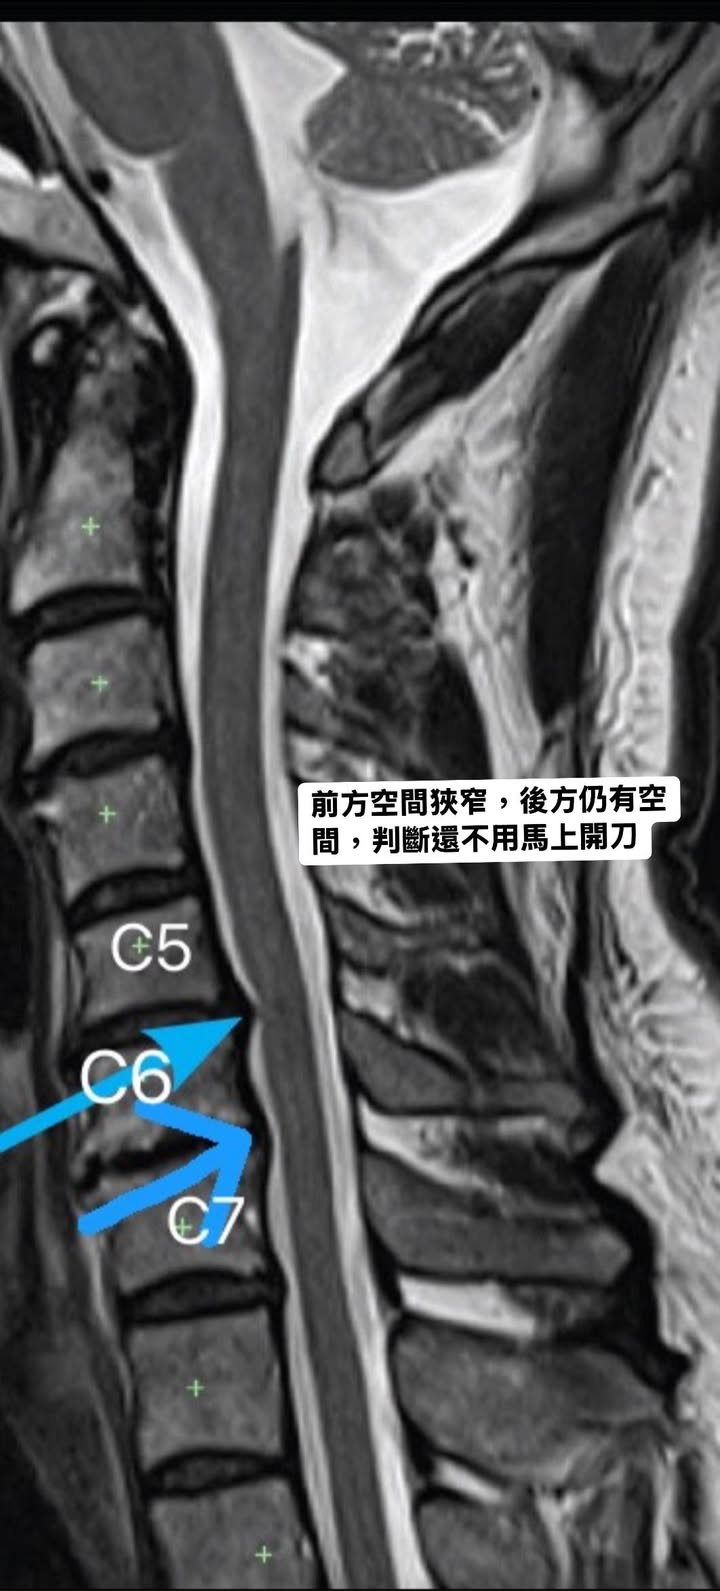

Cervical Spine Treatment Cases 精彩回顧 2024.12.18 2024.12.20 新店區黃先生命運逆轉勝治療紀實 2024.12.24 失散多年的表弟居然來找我治療 2024.12.25 跨海萬里從矽谷到台北的國際醫療外交 2024.12.25 痛起來要人命的腰椎滑脫卡壓神經根醫案 2024.12.26 2024.12.28 2024.12.30 五湖四海的信任之跨越四年的追蹤 2025.01.02 88歲老母的奇蹟之旅從輪椅到迪士尼的一萬步 2025.01.05 2025.01.06 七十歲北投張阿姨頸椎壓迫與劇痛醫案 2025.01.07 2025.01.08 2025.01.11 2025.01.12 ← 上一頁 27 28 29 30 31 下一頁 →